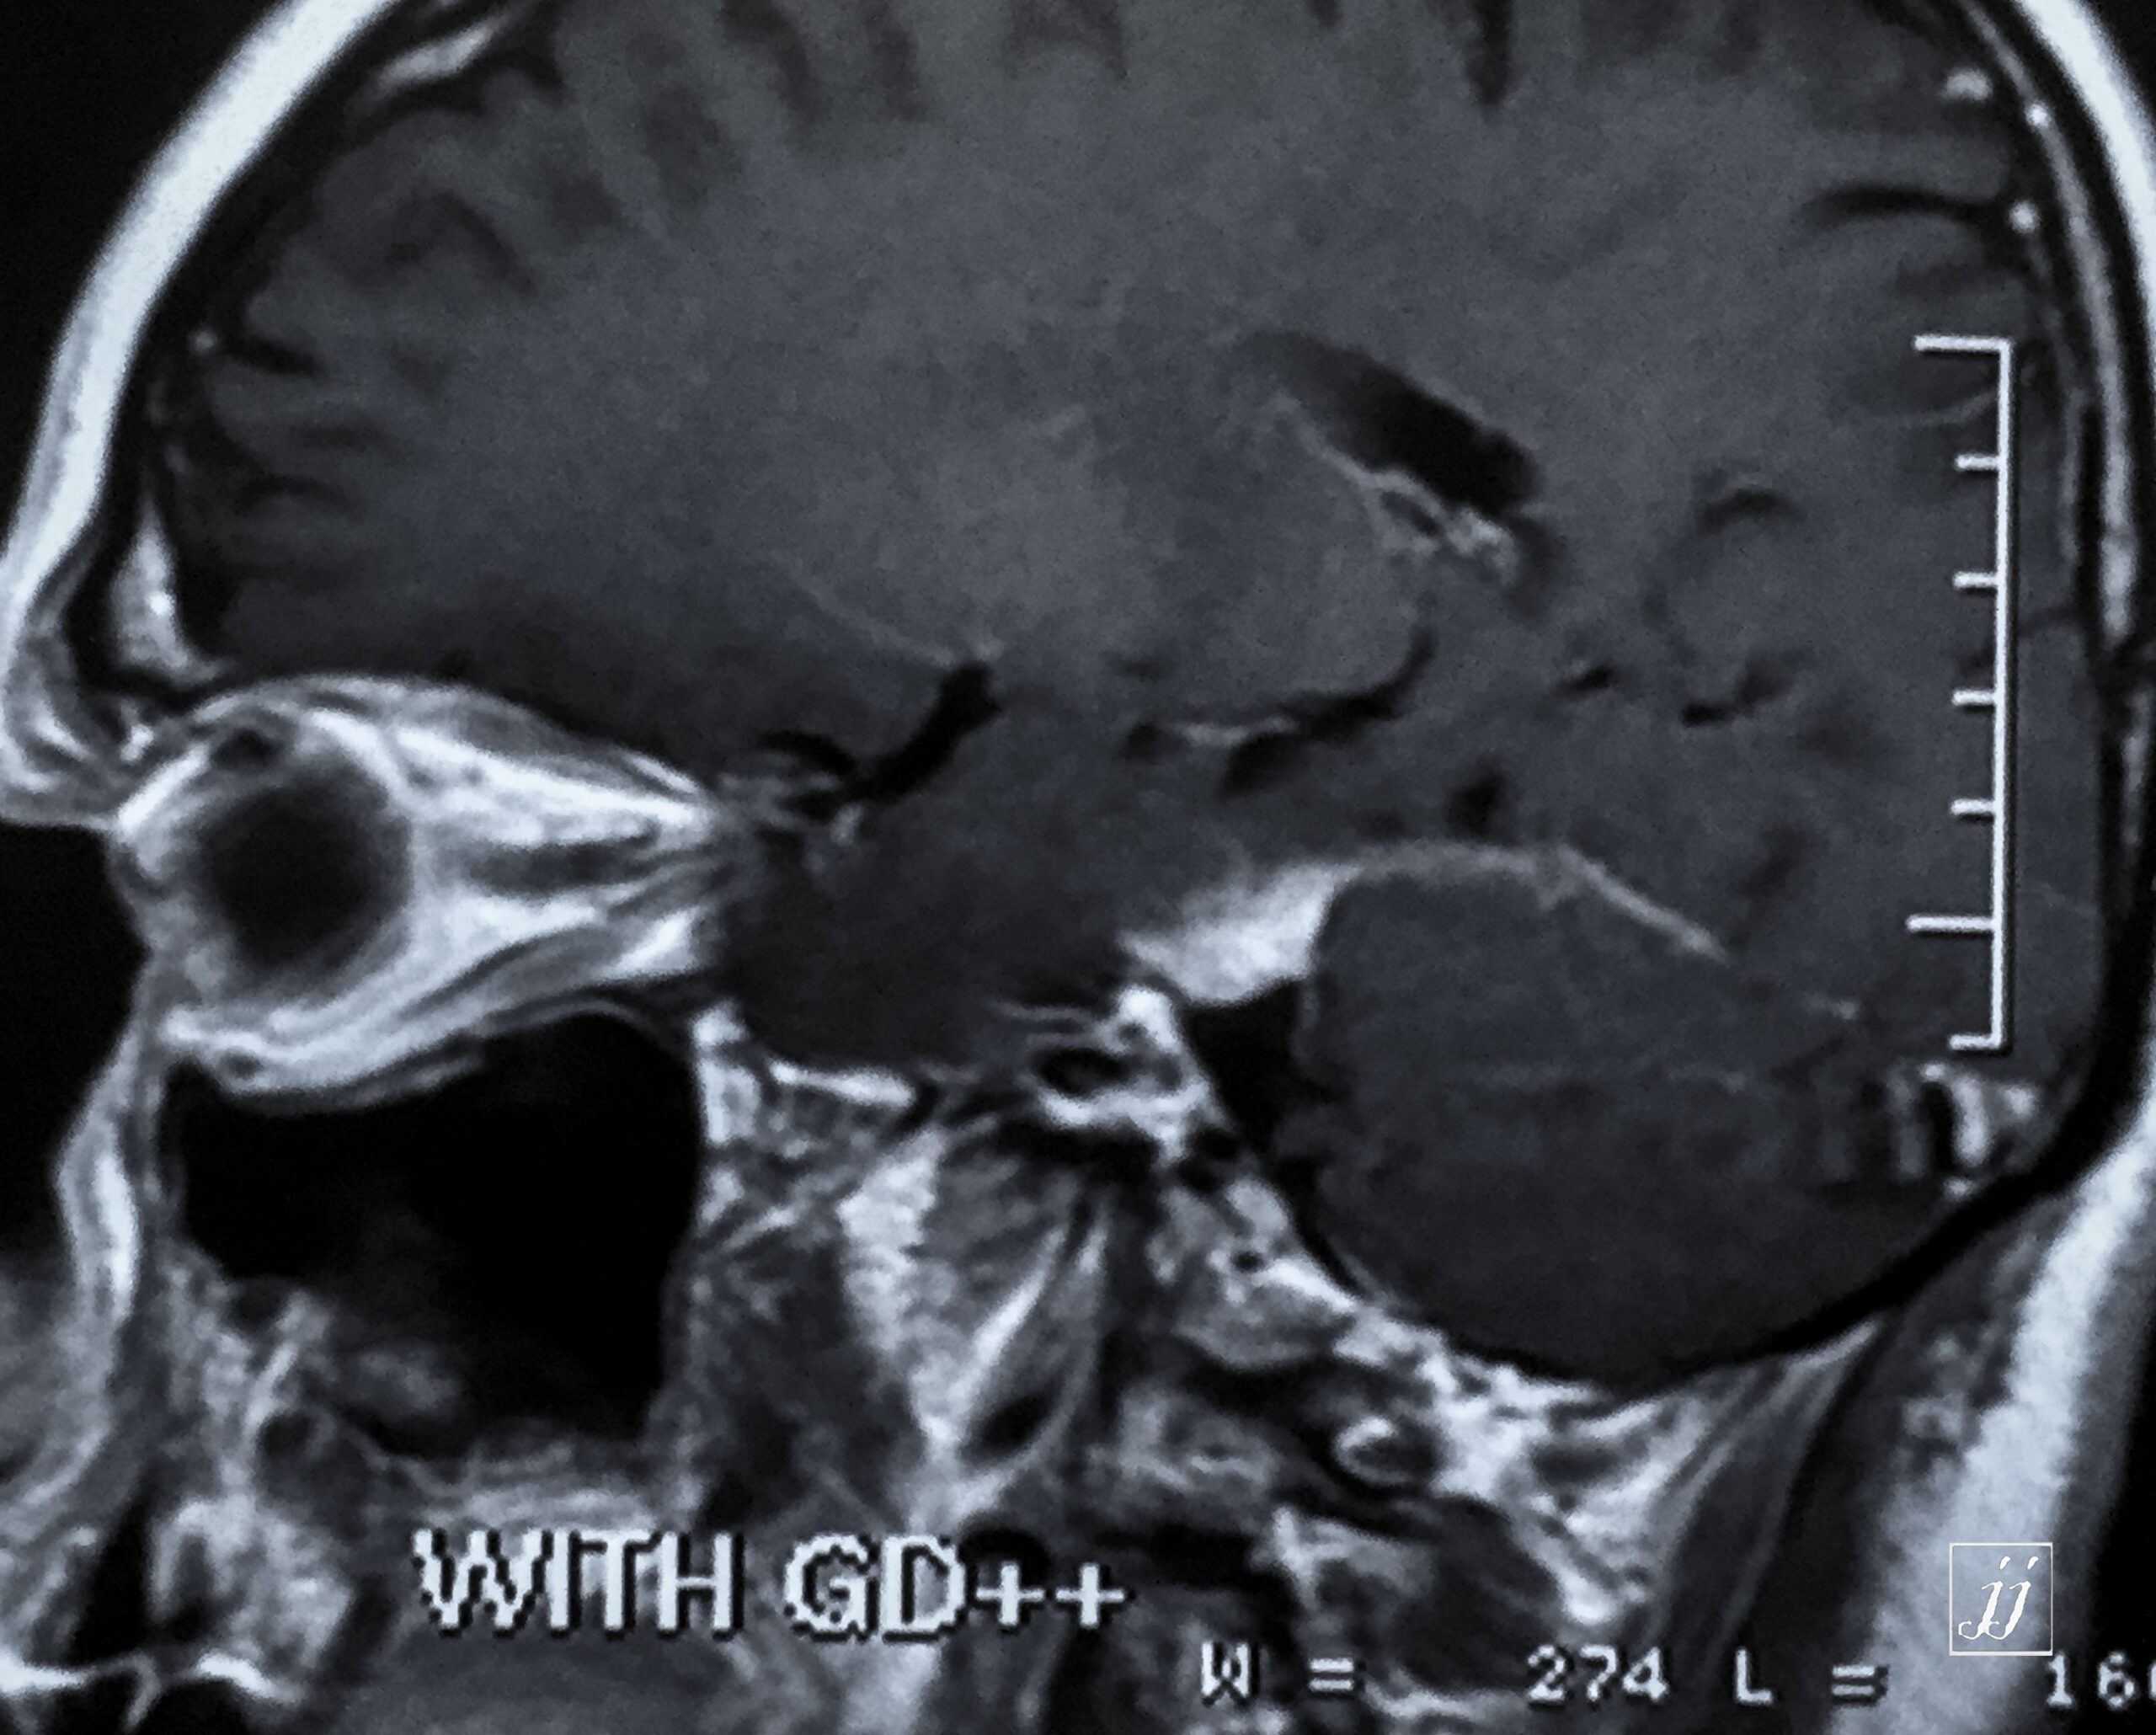

Brain- small right CPA Meningioma (3)